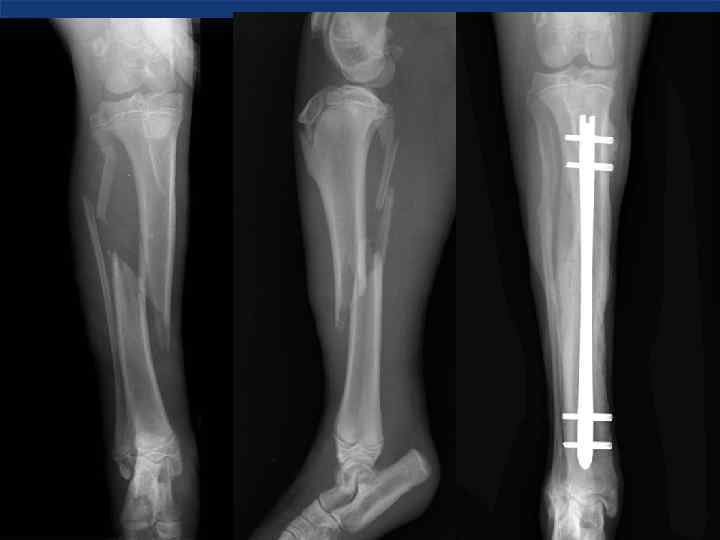

Интрамедулярный штифт Интрамедулярный штифт

Интрамедулярный остеосинтез • Фиксация перелома интрамедулярным штифтом с запирающим винтом. – Такой фиксатор успешно Интрамедулярный остеосинтез • Фиксация перелома интрамедулярным штифтом с запирающим винтом. – Такой фиксатор успешно противостоит всем силам действующим на перелом.